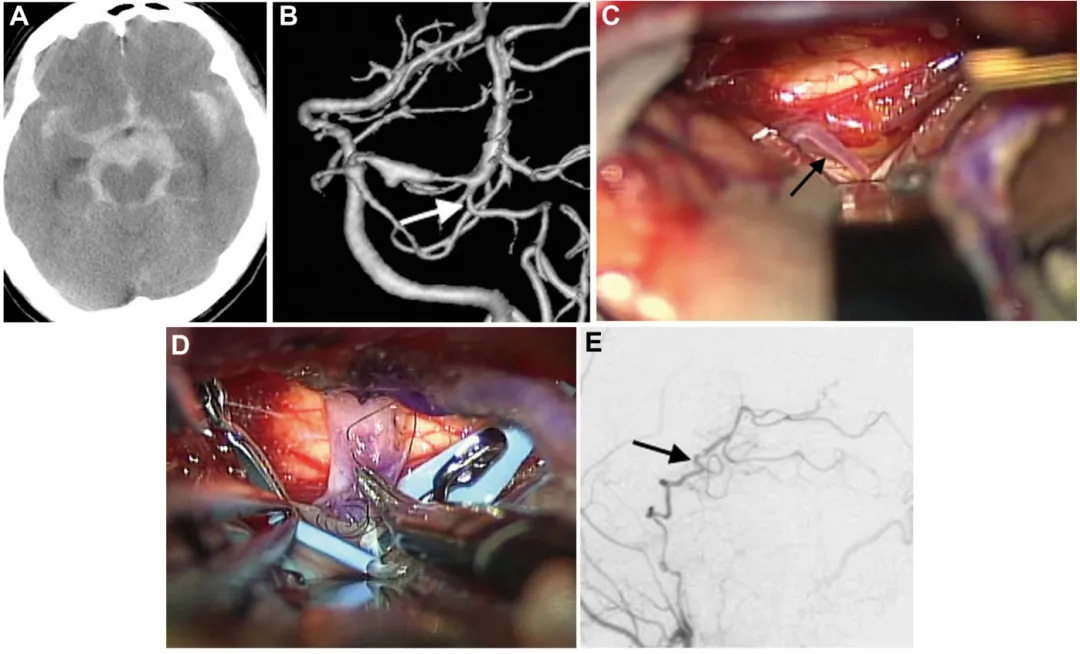

一位47岁男性因蛛网膜下腔出血入院(图A),后续检查发现左侧P1-P2段夹层动脉瘤(图B)。情况危急,医生通过左侧颞下入路,选择后颞动脉作为受体(图C、D),成功完成搭桥和孤立术。患者康复出院,一年后恢复至正常状态。

病例2详细资料:术前影像(A、B)、术中照片(C、D)及术后血管造影(E)

A. CT显示弥漫性蛛网膜下腔出血,左侧脑桥前池增厚明显;

B. 出血后18天血管造影显示左侧P1-P2段扩张伴狭窄特征,颞后动脉自狭窄病变远端发出(箭头标注);

C、D. 选择颞后动脉(箭头标注)作为受体动脉,经左侧颞下入路用连续缝合行颞浅动脉-颞后动脉吻合;

E. 术后1周颈外动脉血管造影显示,通过分流血管,整个左侧大脑后动脉供血区血流良好(箭头标注)。